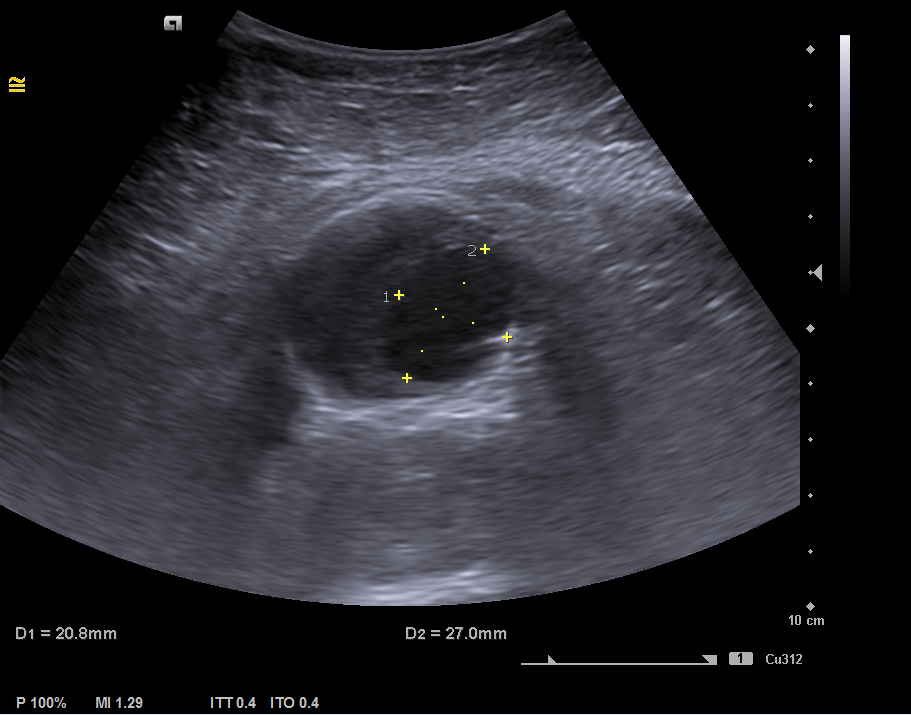

En la ecografía clínica se observa la aorta abdominal con calibre aumentado de tamaño (46 x 41 mm de diámetro), trombo mural interior y luz del vaso de 20 x 27 mm compatible con aneurisma de aorta abdominal fusiforme que se extiende hasta bifurcación aortoilíaca. Arterias ilíacas comunes sin datos de afectación.